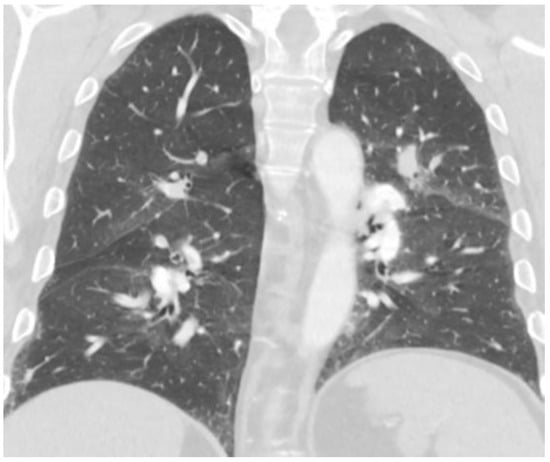

2. Case Report